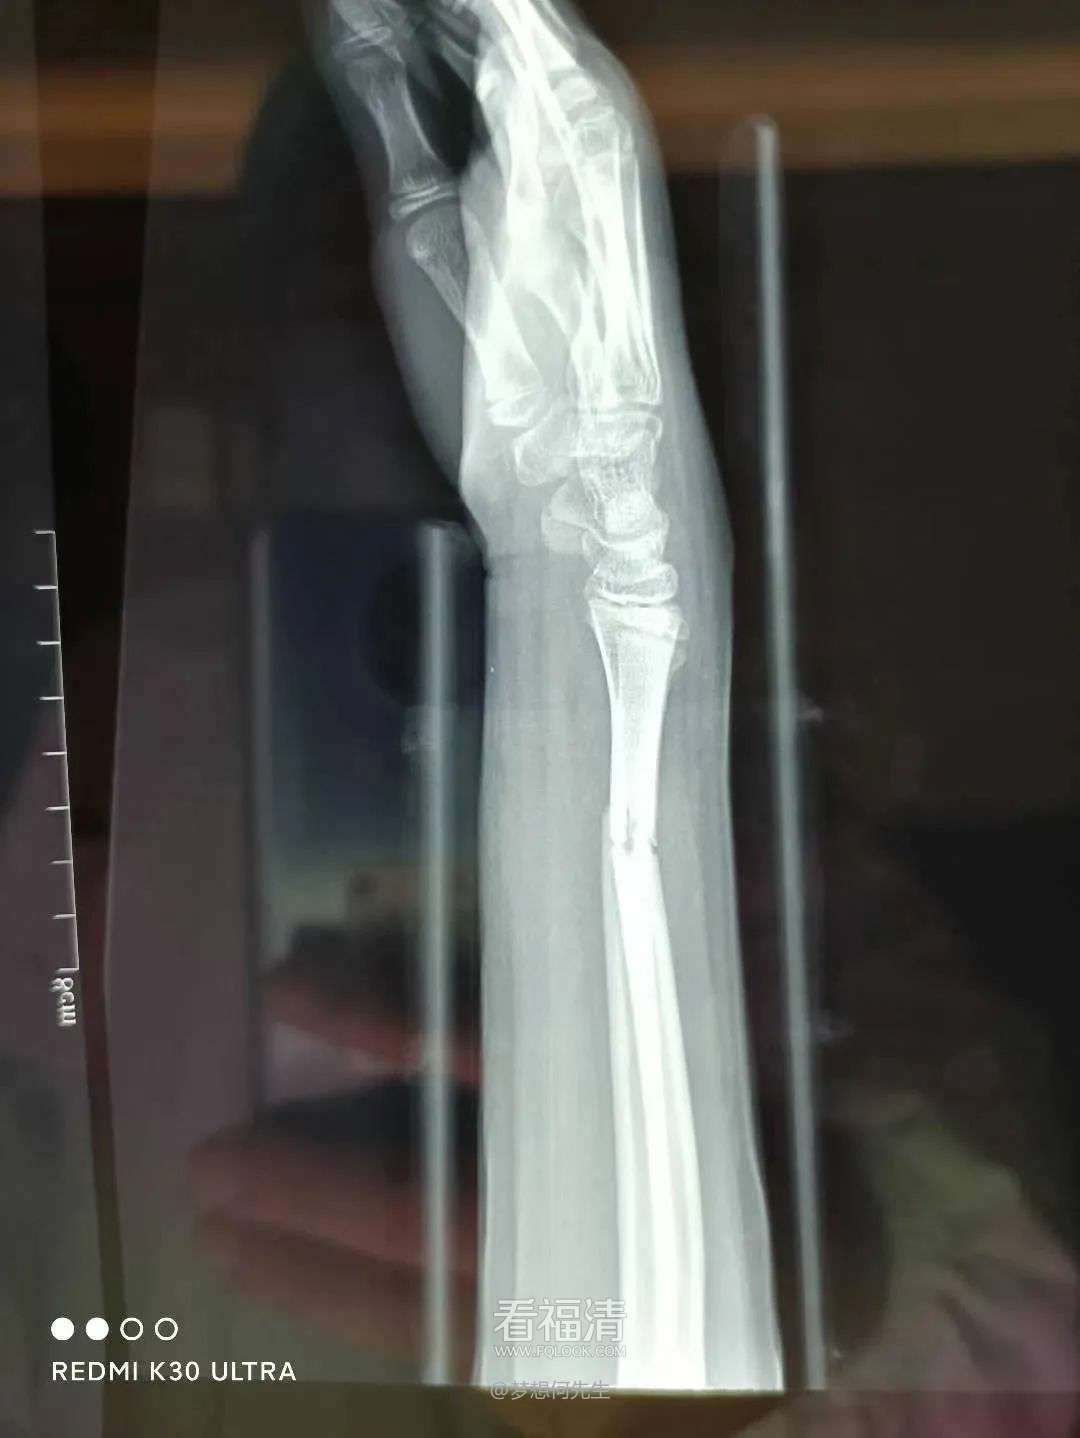

患者为53岁男性,因不慎跌倒,右上臂遭受重创,出现明显的畸形、肿痛以及活动受限。他迅速前往当地医院寻求治疗,经过详细的拍片检查后,被诊断为右肱骨干多段骨折。对此,医师原本建议通过手术治疗来确保患者的康复。然而,该患者由于患有肝硬化,导致凝血功能严重受损,无法接受手术治疗。因此,在伤后四日,患者转至福清市第五医院,希望找到更为合适的保守治疗方案。

第一次拍片

复位后拍片

王征勇接诊后,凭借丰富的临床经验,对患者的病情进行了全面而细致的评估,采用手法复位结合小夹板外固定的方式来进行治疗。随后的影像学检查复查结果显示,患者的骨折对位对线情况良好,但有一处较大的骨片出现了分离移位。王征勇再次进行了审慎的评估,认为当前的对位对线状态是适宜的,可以继续采取保守治疗措施。